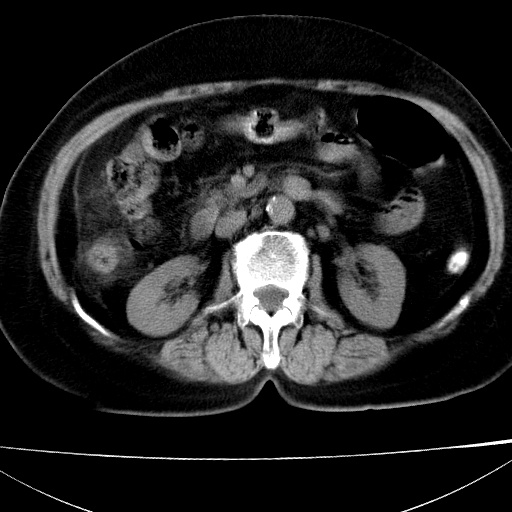

患者女74岁;右上腹胀痛1月,伴恶心,无发热;生活在疫水区。有术后病理及术后半年的追踪ct.

1)慢性血吸虫病(典型)。2)肝硬化。3)肝癌?4)胆囊炎。5)少量腹水。6)右侧少量胸腔积液。

支持.边缘见高密度线条样钙化影.

肝脏体积缩小,肝裂增宽,边缘不平呈波浪状,肝右叶见分隔状条索形钙化,亦见多结节低密度灶,边界不清,肝周可见少许液性暗区,胆囊增大内密度均匀,脾脏下缘低于脏脏的下缘,胸腔亦见液性暗区,余未见明显异常.

诊断:1肝硬化并慢性吸血虫病,脾肿大

2肝内占位,考虑肝癌可能性大,建议做增强

3胆囊炎, 4少量腹水及胸水

胆囊增大饱满,壁增厚。胆囊颈部见软组织密度影。临近肝右叶前段见片状低密度区,病灶下部见条状钙化,少量胸腹腔积液。意见:胆囊颈癌累及肝脏。

病人以胆囊癌手术的,病理结果为中分化腺癌。

现在看看肝右叶内圆形低密度影你们考虑什么呢?

肝内圆形低密度影考虑扩张的胆管

请看3mm重建像如下: